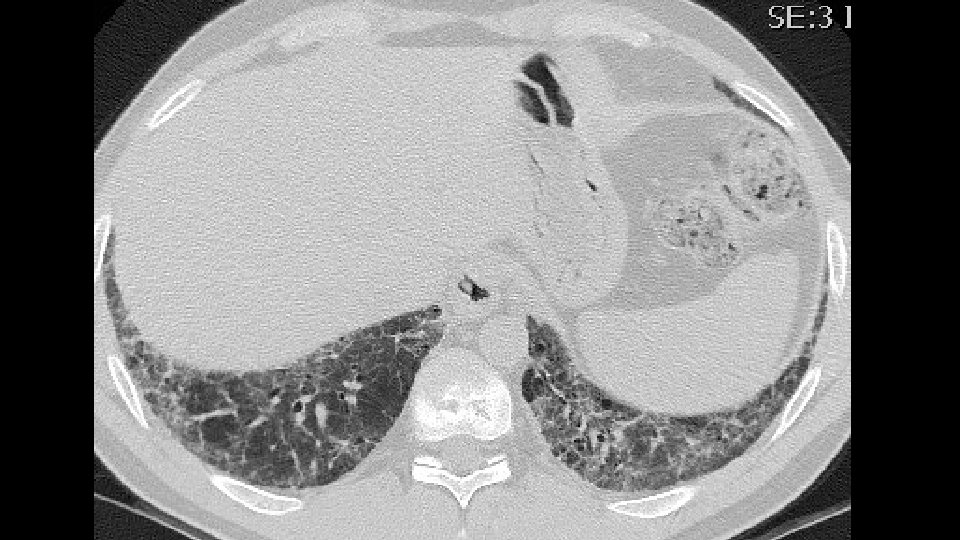

ADDITIONAL HISTORY Patient underwent five cycles of cyclophosphamide (750 mg/mq) EKG and LAB tests: Normal/negative Dyspnea persisted CT scan was repeated seven months later followed by a VATS B

Increase of coarseness

Increase of cysts in the contest of reticulation a ground glass attenuation

Progressive decrease of subpleural sparing

VATS Bx: Fibrosis with honeycombing, in some areas patchy